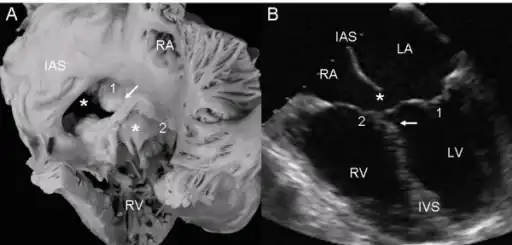

a,b)Atrioventricular septal defect with two separate atrioventricular valves.

Ultrasound showing a complete atrioventricular septal defect